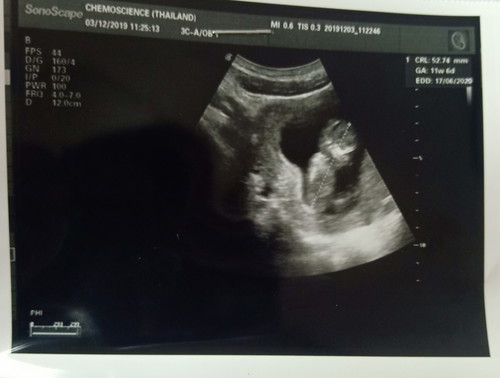

แม่ เพิ่งท้อง ได้ 3 เดือนจ้ะ จากฟิล์ม อัลตร้าซาวด์นะ เห็น ตัวอักษร GA ไหมคะ ขึ้นเป็นตัวเลข 11 W 6 D

จากอัลตราซาว ตอนนี้ อายุครร 11 วี้ค 6วัน ก้ประมาน สามเดือน กำหนดคลอดจากซาว คือ มิย 63